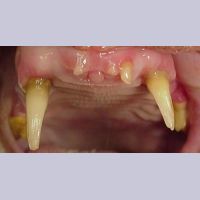

Image 7.15.Persistent primary teeth(유치가 남아있는 덧니인가요?)

Image 7.16. 일반적인 송곳니